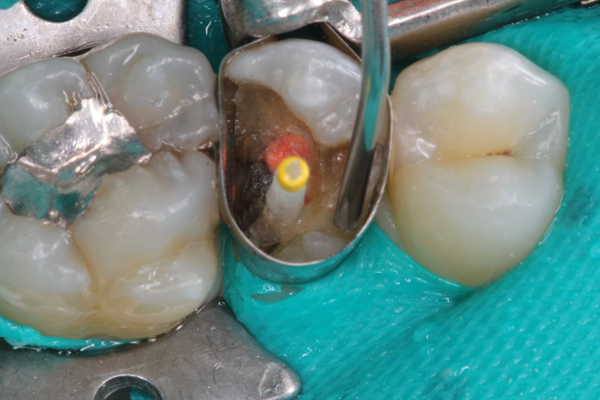

(5.) Placement of composite into tooth No. 19.

Figure 5

Higher viscosity bulk-fill composites can be used up to the occlusal surface, however. Two clinical cases using the bulk-fill composites Tetric EvoCeram Bulk Fill and SonicFill are presented in Figure 2 through Figure 6. Limitations when placing a high-viscosity bulk-fill composite include difficulty of condensing and esthetic restraints. Condensing a high-viscosity resin composite ensures adequate adaptation to the tooth preparation and sufficient interproximal contacts. Condensing 4 mm of composite is more difficult than condensing 2 mm. To ensure adequate interproximal contacts, a sectional or circumferential matrix with an inciso-gingival curvature can be used to obtain a tight area of contact gingival to the marginal ridge. A ring should be used to help separate the teeth and improve the tightness of the contact area.